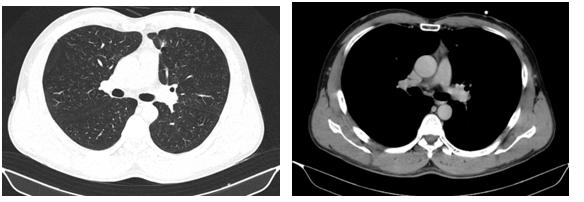

- Chụp cắt lớp vi tính lồng ngực: phim trước điều trị

Hình 1. Trên phim chụp CT lồng ngực ở cửa sổ nhu mô: thùy trên phổi trái có khối đặc tròn bờ tua gai, kích thước: 29 x20mm, kính mờ và dày kẽ xung quanh, lân cận có nốt bán đặc kích thước 29 x 17mm, ngấm thuốc không đồng nhất sau tiêm, nghi ngờ có phần xâm lấn trung thất trước. Nhu mô thùy còn lại và nhu mô phổi phải lan tỏa các nốt đặc tròn to nhỏ không đều, đường kính: 2-8mm.

Hình 2. Cửa sổ trung thất: Vài hạch trung thất cạnh khí, hạch lớn nhất kích thước 14x7mm

- Cắt lớp vi tính lồng ngực:

Sau 3 tháng điều trị đích:

- U nguyên phát và u thứ phát ở cả 2 phổi đều giảm kích thước rất nhiều, không thấy hạch trung thất.

Sau 6 tháng điều trị:

- U nguyên phát chỉ còn kích thước rất nhỏ, u thứ phát 2 bên phổi đã mất hết.